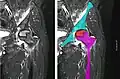

Nuclear magnetic resonance of avascular necrosis of left femoral head. Man of 45 years with AIDS. -

The intravertebral vacuum cleft sign (white arrow) is a sign of avascular necrosis. (Avascular necrosis of a vertebral body after a vertebral compression fracture is called Kümmel's disease.[13])